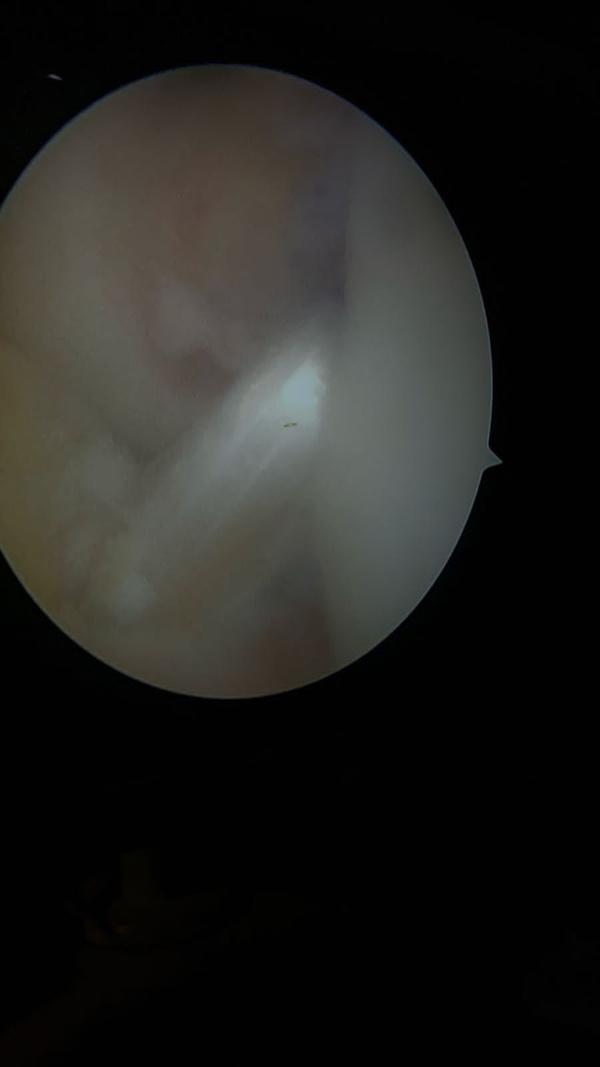

🏥 ACL Surgery: What to Expect 🏥 If you're facin...

View DetailsBest Arthroscopic Surgeon in Vile Parle Best A...